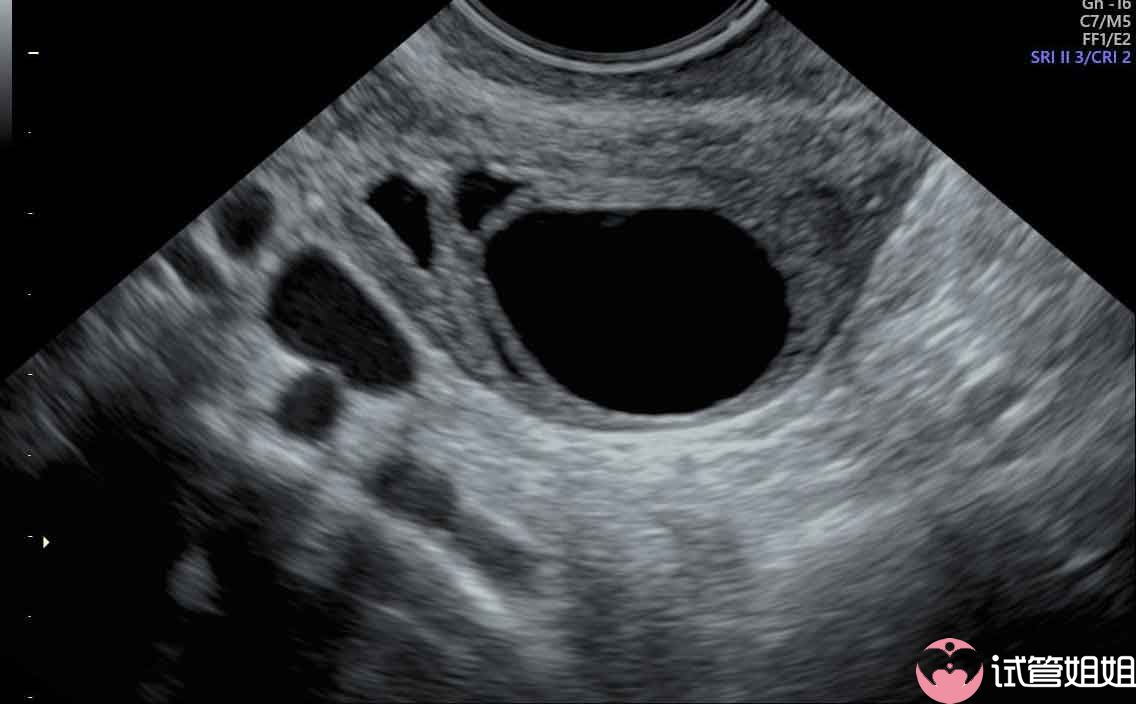

准妈妈卵泡个数